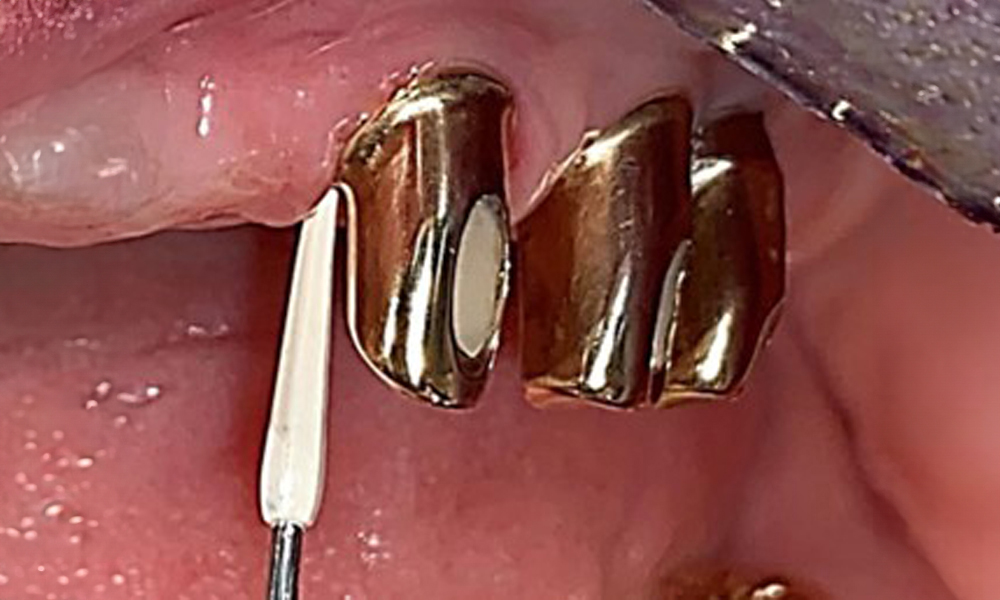

На пациентката е поставена комбинирана подвижна горночелюстна телескопична протеза преди повече от 25 години (фиг. 1, фиг. 2, фиг. 3) и тя е много доволна от протезите си. Пациентката има адекватна фиксирана протеза за долната челюст (фиг. 4).

Денталните открития са следните: Комбинирани снемаеми протези на импланти и телескопични протези, поддържани от зъби, на импланти 15, 13, 21, 23, 24, 25 и зъб 11 (фиг. 1, фиг. 2, фиг. 3). Пациентът е снабден с фиксирана долночелюстна протеза. Над зъби 37-34 и 45-47 бяха налични адекватни мостове (фиг. 4), краищата на коронките бяха интактни и нямаше активен кариес. Върху зъб 43 имаше композитна пломба с маргинална празнина. Имаше рецесия на долната гингива, която разкриваше от 1 до 3 mm от кореновата повърхност. Това се отнася и за 11.